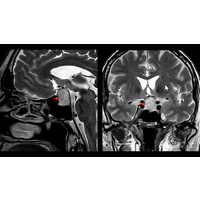

Neben den genannten hypophysären Steuerhormonen TSH (Schilddrüse) und ACTH (Nebenniere), produziert die Hypophyse noch viele weitere Steuerhormone. Hiervon ist das Wachstumshormon (GH) zu nennen. Liegt hier ein Hormonexzess vor (z. B. bei einem hormonaktiven Hypophysentumor, Abbildung 2) kommt es zum Krankheitsbild der Akromegalie. Bei Kindern kommt es zum sogenannten Riesenwuchs, Gelenkschmerzen und Schwitzen. Bei Erwachsenen verändert sich nicht nur das Aussehen mit vergrößerter Nase, prägnanten Wangenknochen, überdimensionierten Händen und Füßen, sondern auch zur Schädigung innere Organe und zu Herzerkrankungen. Weitere typische Zeichen der Akromegalie sind ein Auseinandertreten der Zähne im Unterkiefer, Vergrößerung der Zunge und tiefe Stimme.

Abbildung 2: Magnetresonanztomografie eines Hypophysenadenoms (Quelle: Deutsche Gesellschaft für Endokrinologie).

Im Rahmen der Labordiagnostik erfolgt die Bestimmung des Insulin-like growth factor-I (IGF-I), welcher unter dem Einfluss des Wachstumshormons in der Leber gebildet wird und viele Wirkungen des Wachstumshormones vermittelt. Mittels eines MRTs wird ggf. ein Tumor in der Hypophyse nachgewiesen.